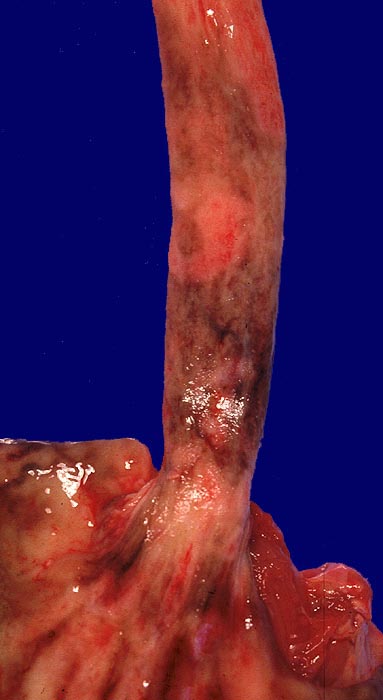

PathoPic ID 1466 - Erosion bei Soorösophagitis

Erosion bei Soorösophagitis

Multiple konfluierende braun verfärbte Erosionen der Ösophagusschleimhaut.

Soor mikroskopisch im Bereich der Erosion. Alkoholische Leberzirrhose.